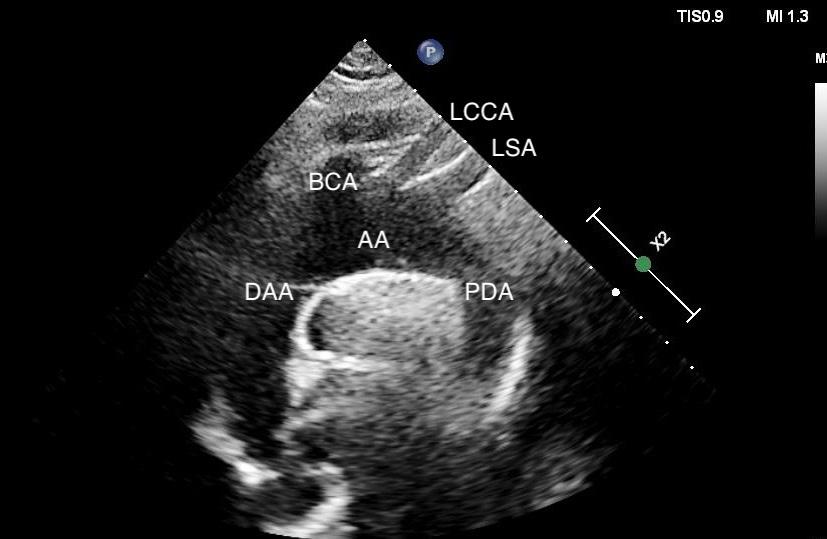

In the case covered in this article, an 85-year-old man with septic shock caused by a perforated sigmoid colon was profoundly hypovolemic and required crystalloid resuscitation and dual vasopressors. Ultrasound revealed that his internal jugular vessels were completely collapsible. Initial attempts to place the catheter were unsuccessful due to vessel collapse. The Trendelenburg position did not adequately dilate the internal jugular vein, as shown in Image 1. However, using a passive leg raise, significant dilation of the internal jugular vein was observed, enabling successful cannulation (Image 2).